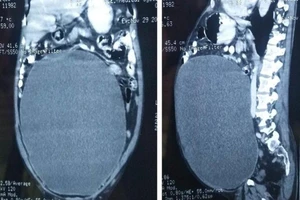

Bàng quang tích 11 lít nước do bị tiểu đường